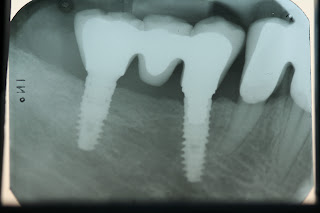

| ΑΚΤΙΝΟΓΡΑΦΙΑ ΜΕΤΑ |

Η Εμφυτευματολογία είναι ένα κλάδος της Οδοντιατρικής που

ασχολείται με την τοποθέτηση και τη διατήρηση στη στοματική κοιλότητα των οστεοενσωματούμενων

οδοντικών εμφυτευμάτων. Τα οδοντικά εμφυτεύματα είναι υποκατάστατα δοντιών από

τιτάνιο, ένα βιοσυμβατό υλικό, που τοποθετούνται στο οστούν της γνάθου για να

υποστηρίξουν αποκαταστατικές οδοντιατρικές εργασίες όπως κορώνες, γέφυρες ή

οδοντοστοιχίες. Σε περιπτώσεις μη επάρκειας οστικού υποστρώματος για τοποθέτηση

εμφυτευμάτων πραγματοποιείται οστική ανάπλαση πριν ή ταυτόχρονα με την

τοποθέτηση του εμφυτεύματος.